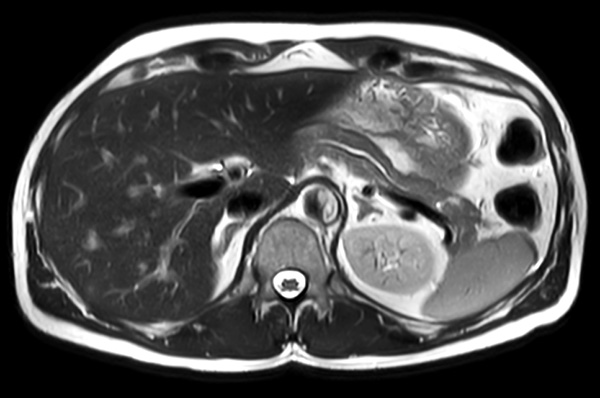

Axial T2w MultiVane XD (high res)